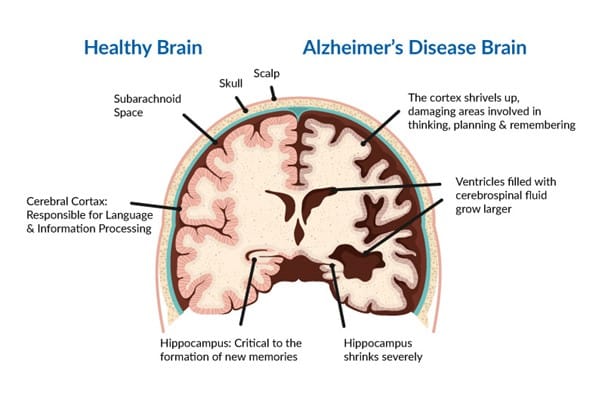

Alzheimer disease is a progressive neurological condition that causes a gradual decline in behavioral and cognitive abilities such as memory, interpretation, language, concentration, and decisions. Alzheimer is the most prevalent dementia, contributing to two-thirds of dementia cases in persons 65 and older.

Although low amyloid and high tau proteins in CSF serve as biomarkers, they are not exclusive to Alzheimer’s disease. A person may function independently in the early stages of Alzheimer’s. He or she may continue to drive, work, and participate in social events.

Despite this, the individual may experience memory lapses, such as forgetting familiar words or placing everyday objects. The progression to mild cognitive impairment can be predicted by increasing tau protein in CSF, right entorhinal cortex thickness, and right hippocampus volume on MRI.

Alzheimer disease is initially associated with decreased memory; nevertheless, the individual may acquire significant cognitive and behavioral symptoms such as depression, rage, anxiety, irritability, sleeplessness, and paranoia with time.